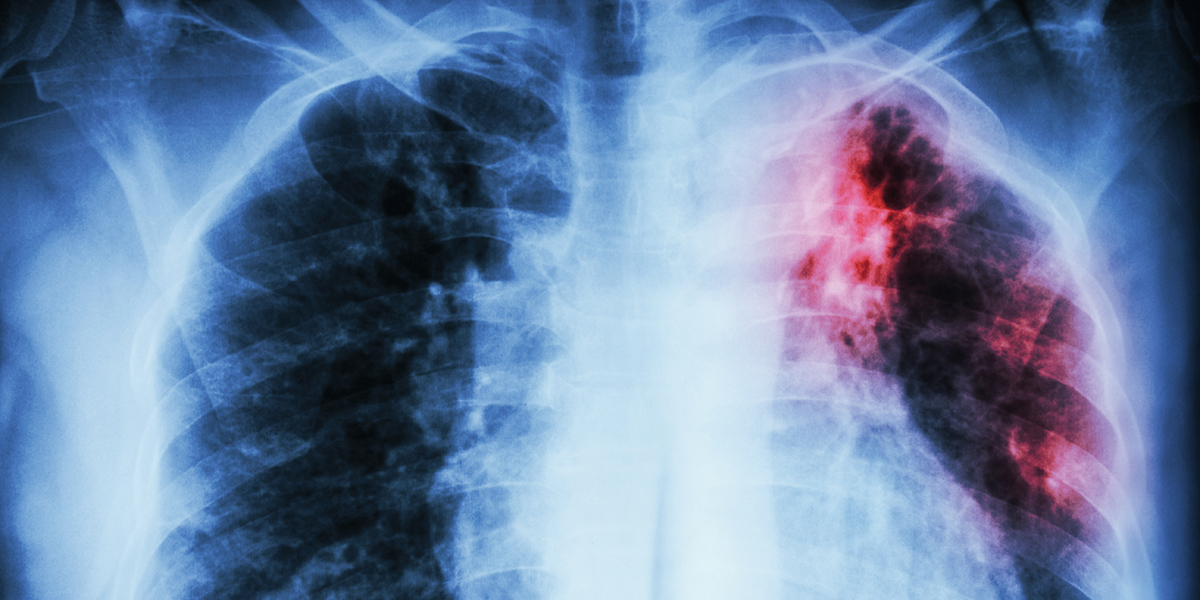

ТОЛЬКО НЕ ЭТО. Из-за недостатка информации люди воспринимают диагноз "туберкулез" как приговор